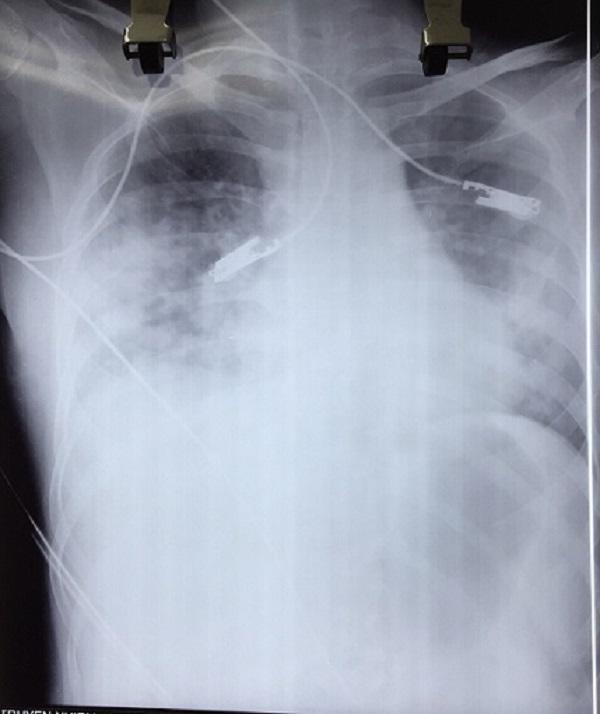

Hình ảnh chụp X-quang viêm phổi của bệnh nhân

Sau khi chuyển xuống khoa Truyền nhiễm 1 ngày, nữ bệnh nhân quê Tuyên Quang này khó thở, thở gắng sức, ho ít, thể trạng suy kiệt… Phim chụp XQ và các xét nghiệm cho thấy bệnh nhân bị biến chứng viêm phổi nặng sau thủy đậu, trên nền lupus ban đỏ hệ thống/hoại tử đầu chi.

Hiện bệnh nhân đang được điều trị tích cực ở khoa, phải thở ô xy, các bác sĩ cho biết, tiên lượng của bệnh nhân rất dè dặt, không dám nói trước điều gì.